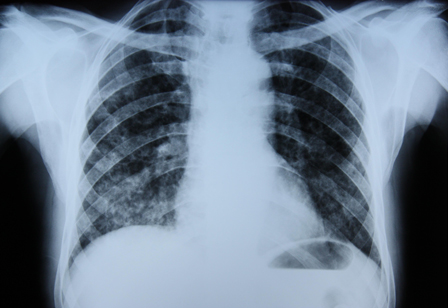

[Figure caption and citation for the preceding image starts]: Posterior-anterior chest x-ray with bibasilar linear interstitial changes consistent with asbestosisFrom the personal collection of Kenneth D. Rosenman, MD [Citation ends].